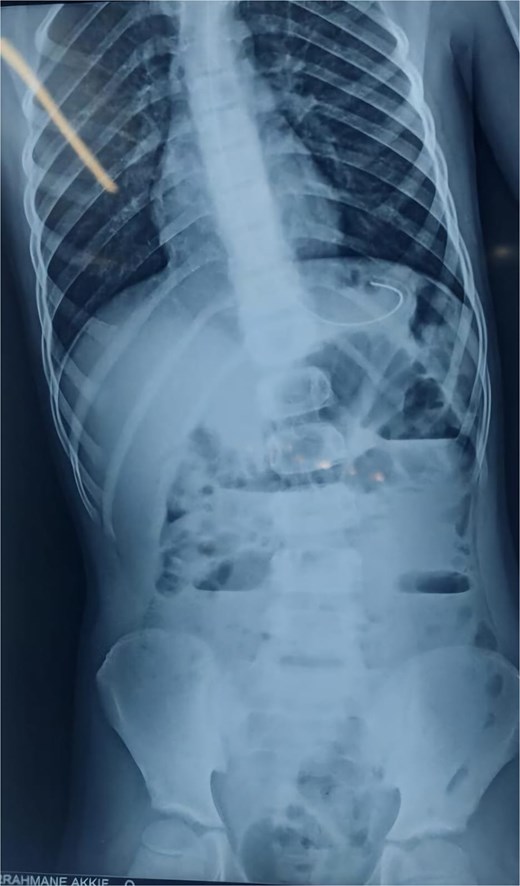

An abdominal X-ray showed multiple dilated bowel loops with air-fluid levels (Figs 1 and 2), consistent with a high-grade intestinal obstruction. Given the patient’s surgical history, a diagnosis of volvulus secondary to intestinal malrotation was strongly considered.

X-ray image at admission showing multiple dilated bowel loops with air-fluid levels.